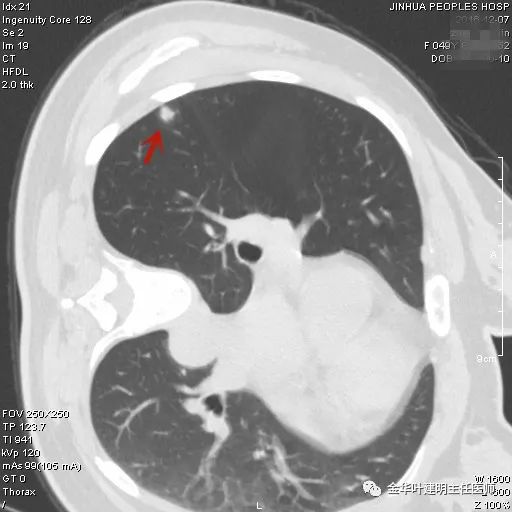

上图是错构瘤,肺良性肿瘤中最常见的类型。一般密度高,边界非常清楚,有时有钙化点或低密度的脂肪区域,但往往典型的少见。有一点是肯定的,就时:边缘非常光滑。如果手术时切开肺实质,它甚至可以像剥花生米一样剥出来。